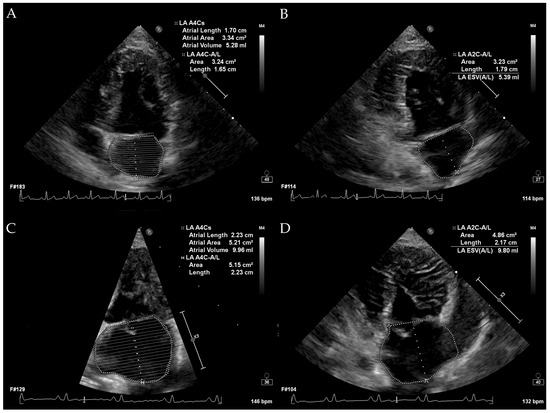

2. Materials and Methods